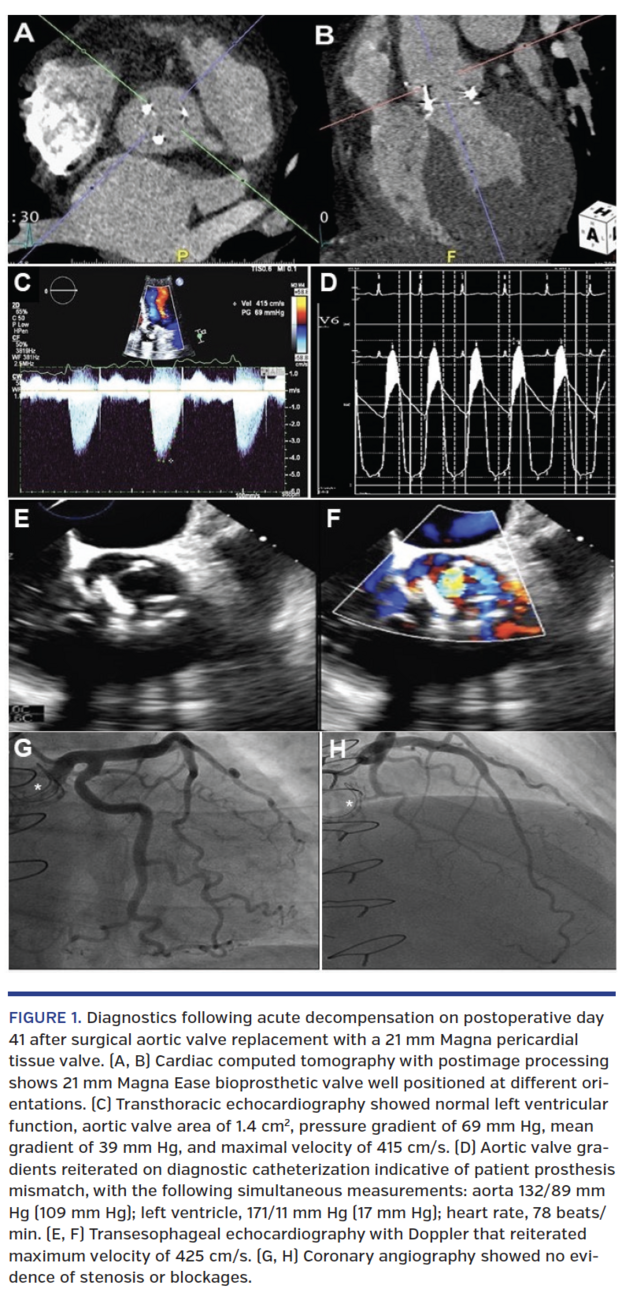

At the time of his outpatient follow-up, the patient’s symptoms were stable at rest, but he noted exertional dyspnea with any activity. He was unable to fully participate in cardiac rehabilitation and was not capable of returning to work as a building contractor. Outpatient evaluation included cardiac computed tomography angiography (Figures 1A and 1B), which showed no evidence of hyperattenuation leaflet thrombosis (HALT) and confirmed valve sizing; transthoracic echocardiography (TTE) was performed 6 weeks after SAVR, with ejection fraction of 70%, mean gradient of 43 mm Hg, and maximal velocity (Vmax) of 400 cm/s, with calculated EOA of 1.19 cm and EOAi of 0.52, consistent with severe PPM (Figures 1C-1F). Transesophageal echocardiography (TEE) showed normal prosthetic valve leaflet function, but revealed an elevated outflow tract Vmax of 425 cm/s. Transseptal left and right heart catheterization with simultaneous pressure measurements showed evidence of moderate to severe aortic stenosis and coronary arteries free of major stenoses or blockages (Figures 1G and 1H). Coronary obstruction risk was predicted to be low with catheter-based therapies, and vascular access was acceptable.